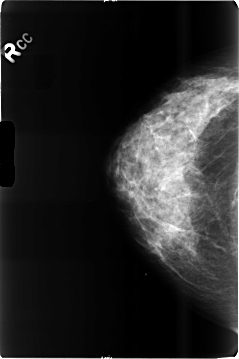

B_3509_1.RIGHT_CC

RIGHT_CC LINES 4664 PIXELS_PER_LINE 3104 BITS_PER_PIXEL 12 RESOLUTION 50 NON_OVERLAY